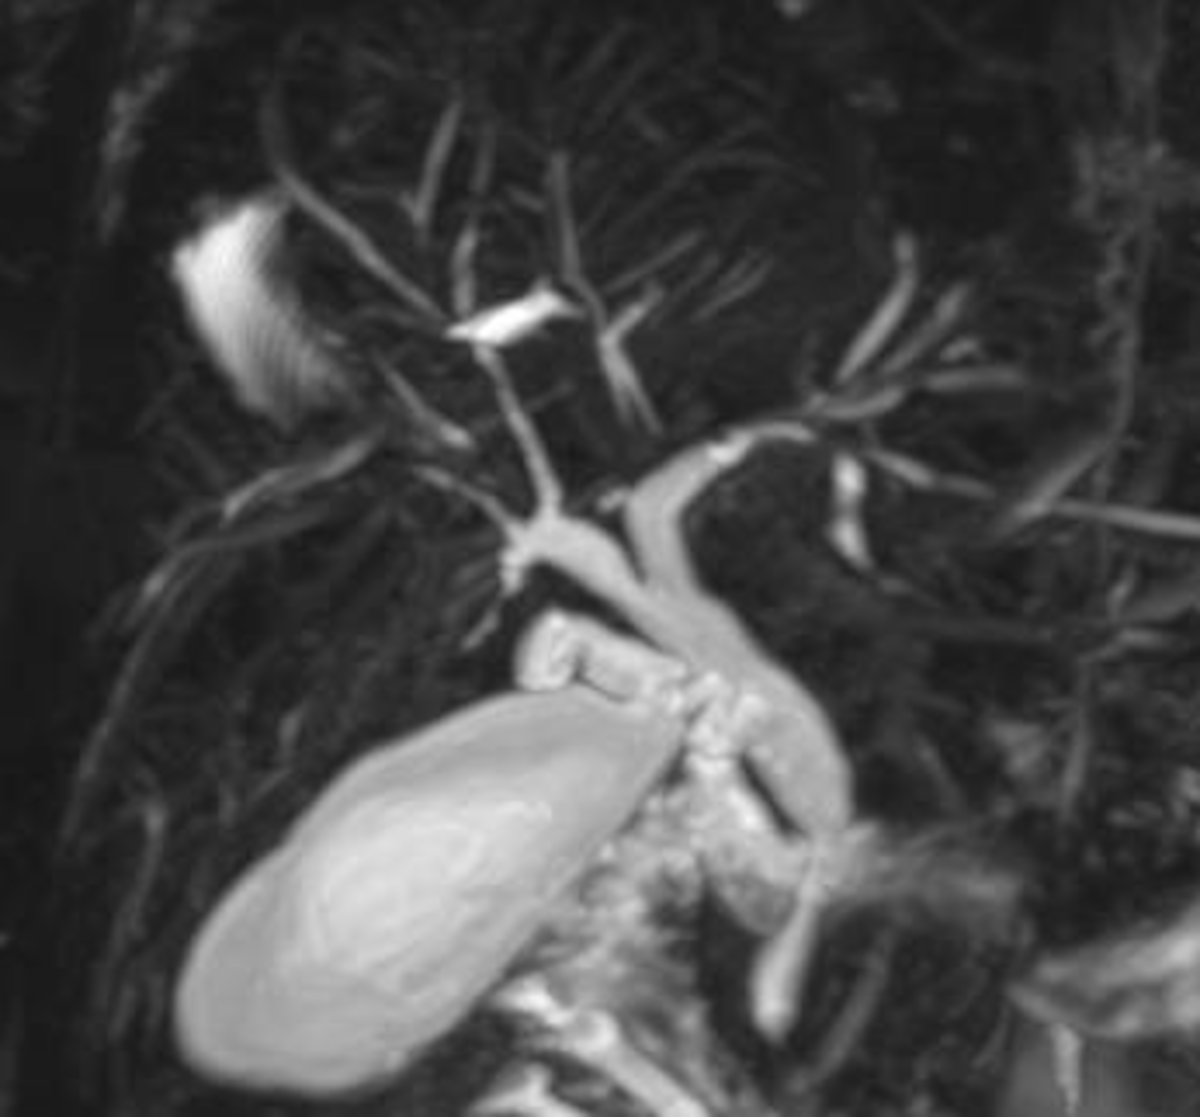

19M, no PMH, w/ abnormal liver function tests. He reports trauma to the abdomen during a fist fight 1 year prior. He has not had jaundice, nausea, or vomiting. Liver tests reveal ALT 78 U/L (normal: 0-35 U/L), AST 72 U/L (normal: 0-35 U/L), total bilirubin 1.4 mg/dL (normal: 0.3-1.2 mg/dL), alkaline phosphatase 240 U/L (normal: 36-92 U/L), and normal albumin. CBC is normal except for a platelet count of 140,000/µL (normal: 150,000-300,000/µL). CT scan reveals hepatomegaly and caudate hypertrophy. A procedure is performed as shown in the figure. What is the best next step in management?

• The patient has Budd-Chiari syndrome with the CT findings supportive of hepatic vein outflow obstruction (caudate lobe hypertrophy as the lobe maintains its direction drainage to the IVC) and venogram showing very diminutive hepatic veins with intrahepatic venous to venous collaterals with a spider web appearance.